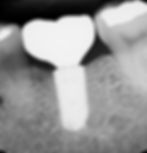

First let me explain what a dental implant is. It's a small titanium post that is inserted into the jawbone, to replace the root of a missing tooth. The implant is then left to fuse with the jawbone over a few months, in a process known as osteointegration. Once the implant has fully fused with the jawbone, it becomes a solid base for attaching a dental crown or bridge.